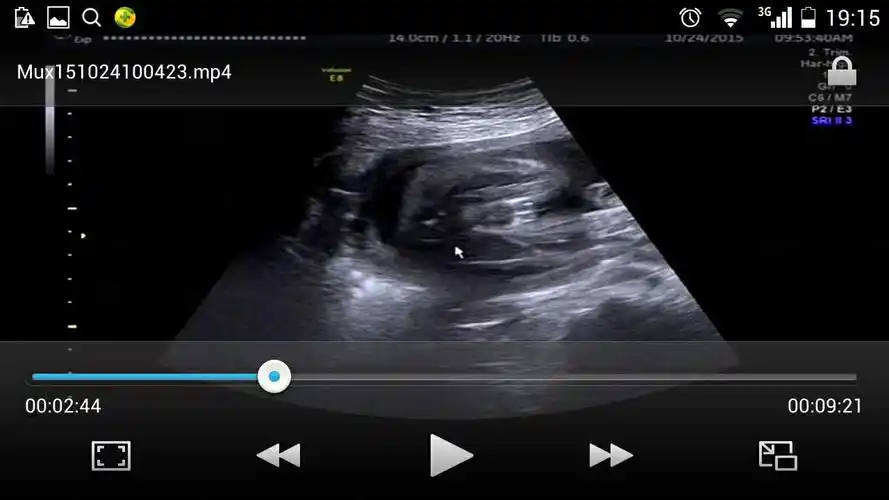

2,四维3个亮点是男孩:怎样可以看出四维彩超上是男孩还是女孩